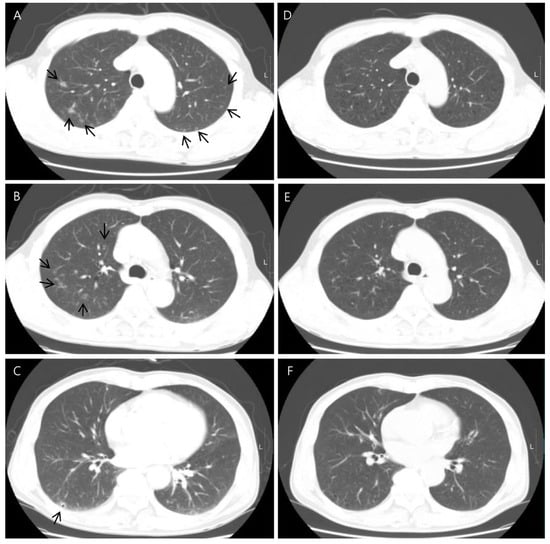

Chest contrast-enhanced CT revealed multiple peribronchial, centrilobular, and cavitary nodules in both lungs (Figure 2), and they have upper lung predominance. The radiologist considered this to be pulmonary metastasis from colorectal cancer first and an infectious condition second. Abdominal CT showed a 2 cm sized, ill-defined lesion in segment 5/6 of the liver (Figure 3). As a differential diagnosis for the solitary hepatic lesion, we considered sclerosing hemangioma, inflammatory pseudotumor, or metastasis. Laboratory results showed only a mild increase in the eosinophil ratio (6.6%). Except for that, no abnormalities were found in the coagulation system or general biochemical tests. Serologic markers for hepatitis B and C, acid-fast bacteria (AFB) stain, and AFP culture were negative. Regarding tumor markers, carcinoembryonic antigen and carbohydrate antigen 19-9 were normal. At that time, he did not take any medication or show signs of infection or other systemic symptoms such as fever or night sweats. In addition, his exact history of previously eating uncooked cow liver or meat is unclear.

Figure 2.

Axial chest CT showed multiple cavitary lung nodules in both lungs with upper lung zone predominance ((A–C), arrows). CT images obtained 5 months after showed the disappearance of the multiple cavitary nodules (D–F).

Liver magnetic resonance imaging (MRI) was performed to differentiate the pulmonary and hepatic lesions from another possible diagnosis. It revealed a 1.5 cm ill-defined nodular lesion contiguously extending into the liver capsule (Figure 4). These findings mostly likely represented liver fluke disease. The diagnosis of toxocariasis was confirmed through the presence of antibodies to Toxocara canis by enzyme-linked immunoassay (ELISA). Other parasite antibody tests, including Clonorchiasis sinesis, Paragonimus westermani, Taenia solium, Spirometra mansoni, Fasciola hepatica, Amoeba, Trichinella spiralis, and Schistosoma, all yielded negative results. Eventually, his colon cancer was treated with laparoscopic low anterior resection. After discharge, the patient took oral albendazole by himself. After 3 months, chest and abdominal CT was performed for the postoperative routine follow-up, and it showed a shrinkage of all pulmonary and hepatic lesions compared to the previous imaging. Finally, after 5 months, the entire multiple cavitary lung and the hepatic nodules disappeared (Figure 2 and Figure 3). In addition, the eosinophil ratio decreased from 6.6% to 0.4%.